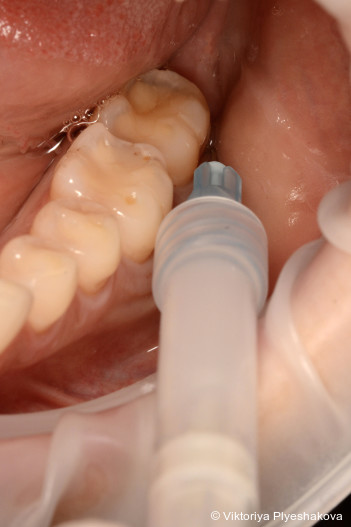

Vor der Instrumentierung wird ein Reinigungsgel aus Aminosäure-gepuffertem Natriumhypochlorit in die Tasche eingebracht. Dieses bewirkt eine deutliche Reduktion der Bakterienpopulation und erleichtert sowohl die Entfernung von Biofilm als auch von infiziertem Granulationsgewebe. Nach der Instrumentierung wird vernetzte Hyaluronsäure eingebracht, um die Gewebereparatur zu fördern, die Heilung zu beschleunigen und so einen Schutz vor erneuter bakterieller Invasion der behandelten Stelle zu verhindern.

Um das Instrumentierungsprotokoll zu verbessern und chi­rurgische Eingriffe zu vermeiden, verwenden wir vor und während der Instrumentierung ein Aminosäure-gepuffertes Na­triumhypochloritgel (Perisolv, Regedent GmbH). Es weicht das entzündliche Granulationsgewebe und die extrazelluläre Matrix des Biofilms auf, wirkt antimikrobiell und verbessert so die Effizienz des Debridements.4 Nach erfolgter Instrumentierung wird vernetztes Hyaluronsäuregel (xHyA – hyaDENT BG, Regedent GmbH) in die Tasche eingebracht. xHyA fördert bekanntermaßen die parodontale Heilung, reduziert Entzündungen und versiegelt so die Stelle gegen erneute Kon­ta­mination.5 Diese Behandlungssequenz wird als Clean & Seal-­Konzept bezeichnet.

Der Behandlungsplan wurde in drei Phasen durchgeführt. In den Pha­­sen I und II wurden die Anweisungen zur Mundhygiene verstärkt, um die Plaquekontrolle zu verbessern, gefolgt von einem supra- und subgingivalen Debridement mit Ultraschall (mectron GmbH) und Hand­instru­menten (Gracey-Küretten). Das Hypochlorit-Reinigungsgel (Perisolv) wurde adjuvant vor und während der Instrumentierung appliziert. Nach erfolgter Instrumentierung wurde vernetzte Hyaluronsäure (hyaDent BG) in die Taschen eingebracht, um die Wunde zu stabilisieren und die Regeneration zu fördern. Nach sieben Tagen wurde eine erneute Applika­tion der vernetzten Hyaluronsäure vorgenommen, um den natürlichen Abbau zu kompensieren, eine sekundäre bakterielle Rekolonisation zu verhindern und einen verlängerten regenerativen Effekt zu erzielen. Die Phase III (Erhaltungsphase) umfasste eine unterstützende Parodontitistherapie alle drei Monate mit Verbesserung der Mund­hygiene und stetiger Überwachung der Sondierungstiefe und des Sondierungsblutens.